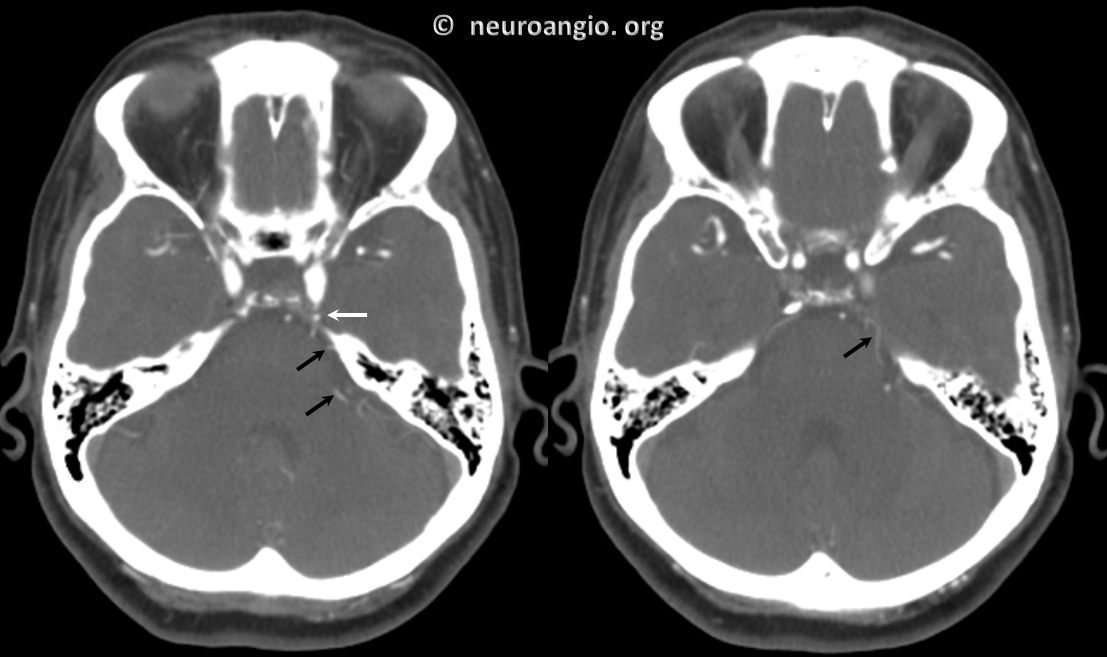

Below is a right PCA (P2) segment embolic occlusion. This is an artery to artery embolus from a diseased right cervical carotid (no arrows needed), via the trigeminal (dashed arrow), into the right P2 (arrow). The anatomy solves the riddle — left PCOM is fetal (no arrows needed), thus left P1 is hypoplastic and embolus of that size would not go there. it also could not have come from the verts because the basilar below trigeminal is hypoplastic as well (arrowhead) — in fact this was originally considered a basilar occlusion. However, clinical presentation was not consistent with that location and basilar hypoplasia below trigeminal is common. Excellent clinical correlation here.